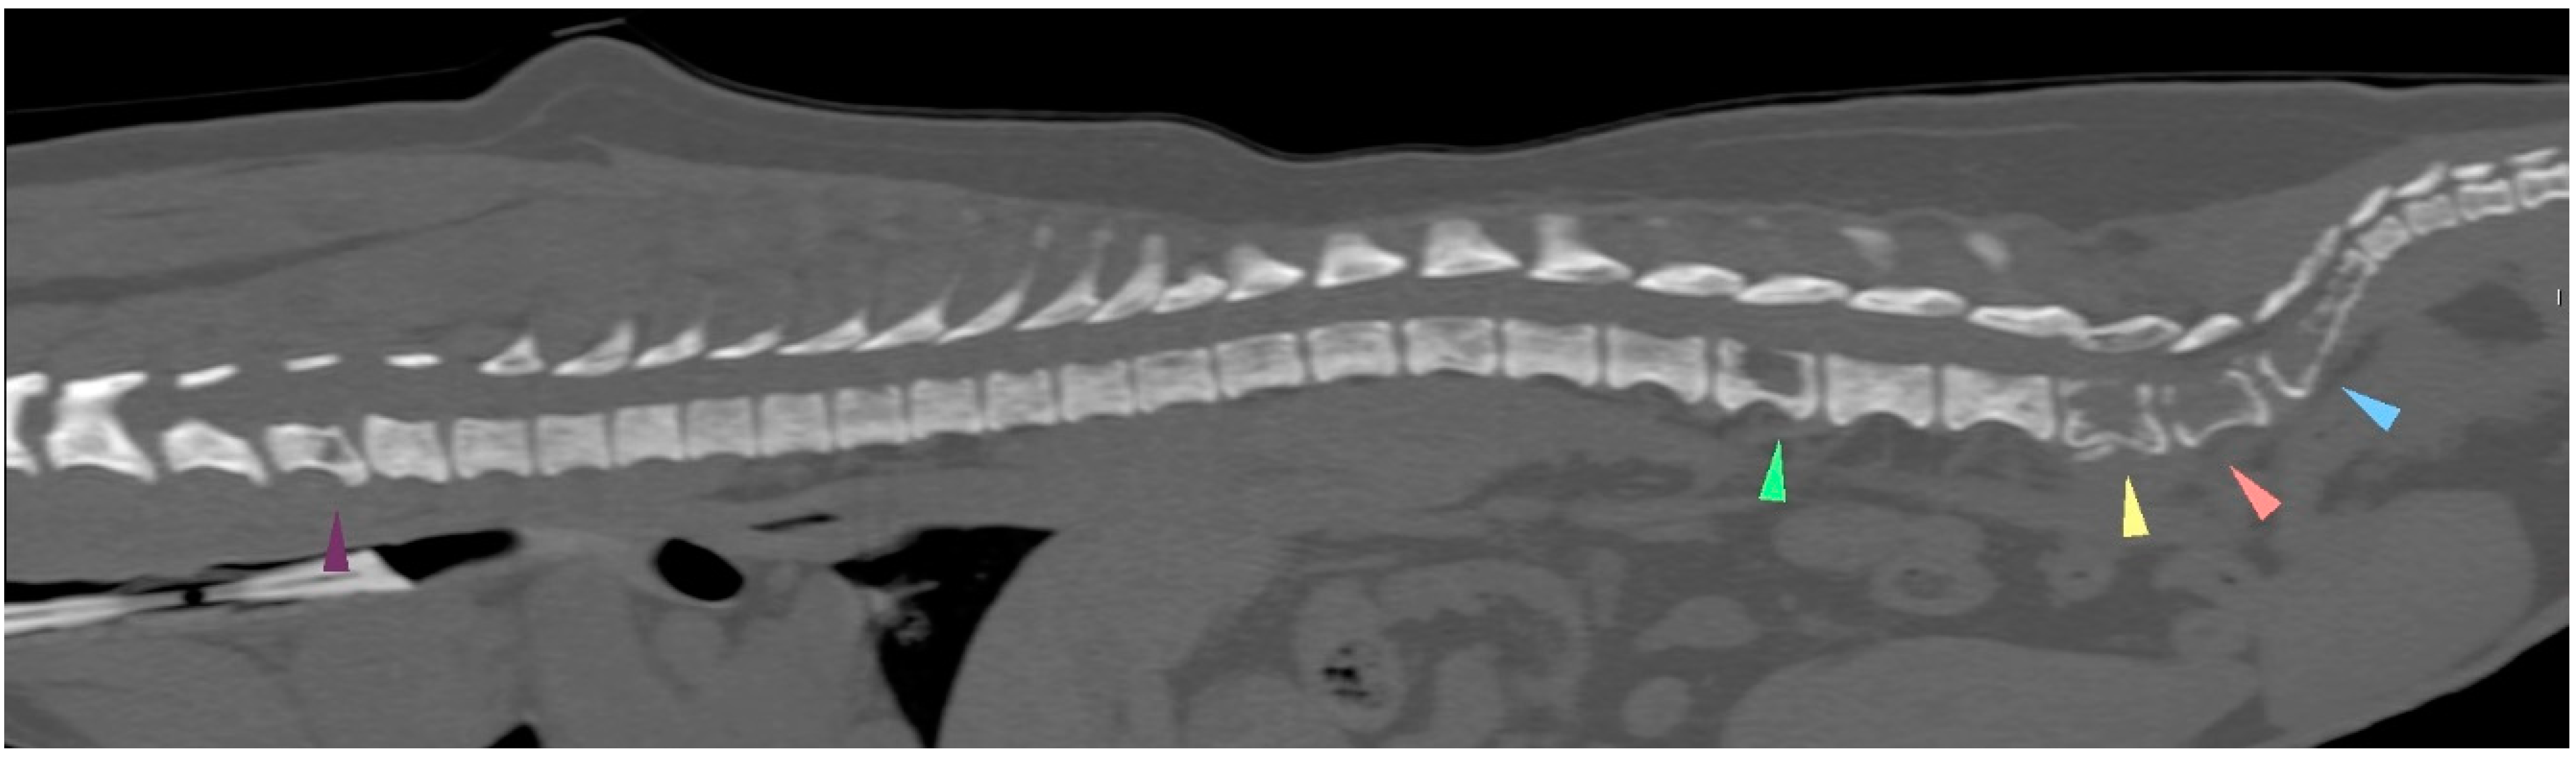

Five weeks after the last carboplatin chemotherapy treatment, firocoxib and toceranib were reinstated despite persistent thrombocytopenia. The presence of a flaccid tail was noted 7 days later, followed by the acute development of posterior paresis within 24 h. A CT examination (Figure 6) revealed several spinal metastases but no other locations of metastases, and the dog died on the next day. In order to respect the owners’ wishes, necropsy was not performed. The time from initial surgery (carried out in our referral center) to death from the mammary tumor was 218 days (7 months and 6 days).

Figure 6.

The CT scan examination at the end. The C6, L3, L6, L7, S1 and S2 vertebral bodies showed cookie-cutter lesions, pointed by the arrows. (The lesion at L6 severely invaded the medullary canal; not shown here).